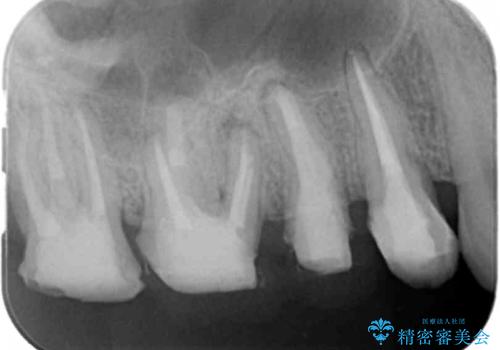

- 近医で「根尖の病変が大きく、残すことができない、歯を抜くしかない。」、と言われ歯を抜く以外の手段がないかを相談しに来院されました。

検査の結果、根管・クリアランス・虫歯といった複合的な問題が認められ、以下のような治療計画を進めることとしました。

根尖病変 →マイクロスコープを用いた精密根管治療の実施